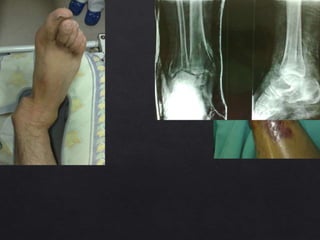

Luxaciones

• Establece si hay fracturas asociadas.

Importancia terapéutica y legal.

• La radiografía simple es de elección.

Rx.

Siempre a dos

planos e inclusive

axial(es).